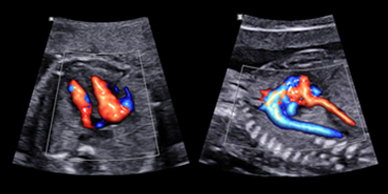

Skanda Advanced Ultrasound Scan Centre starts right from the onset of pregnancy. Our Fetal Medicine experts are concerned with the health of the fetus at every stage – monitoring growth & development; predicting, detecting & managing any complications; and treating congenital disorders & anomalies in the womb itself.